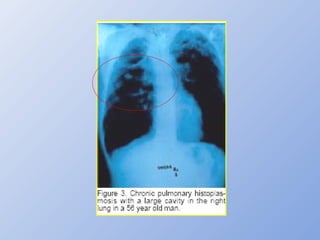

HISTOP. PULMONAR CRÔNICA (HPC)

• Adultos c/ DPOC, eg tabagistas  50 anos

• Fat. predisponente: defeito na arquitetura pulmonar →

impede resolução da micose

• Q. clínico (febre, tosse, escarro purulento ou hemoptóico,

perda de peso, dispnéia, dor torácica)

• Evolução de anos, c/ progressão/remissão

• RX: envolvimento simétrico, ápices, cavitações